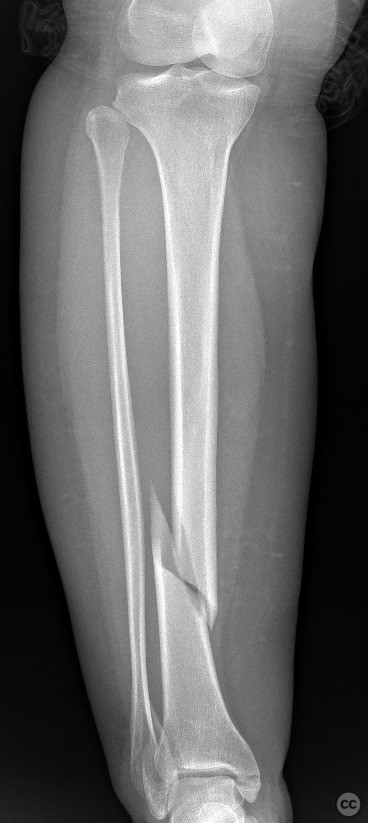

Clinical and radiological findings:  A 45-year-old male sustained a high-energy trauma resulting in an ipsilateral closed tibial shaft fracture and a trimalleolar fracture of the ankle. Initial radiographs demonstrated a displaced mid-diaphyseal tibial fracture (AO/OTA 42-A3) and a trimalleolar ankle fracture (AO/OTA 44-C1), with involvement of the medial malleolus, lateral malleolus, and posterior malleolus. No evidence of open injury or neurovascular compromise was present on examination.